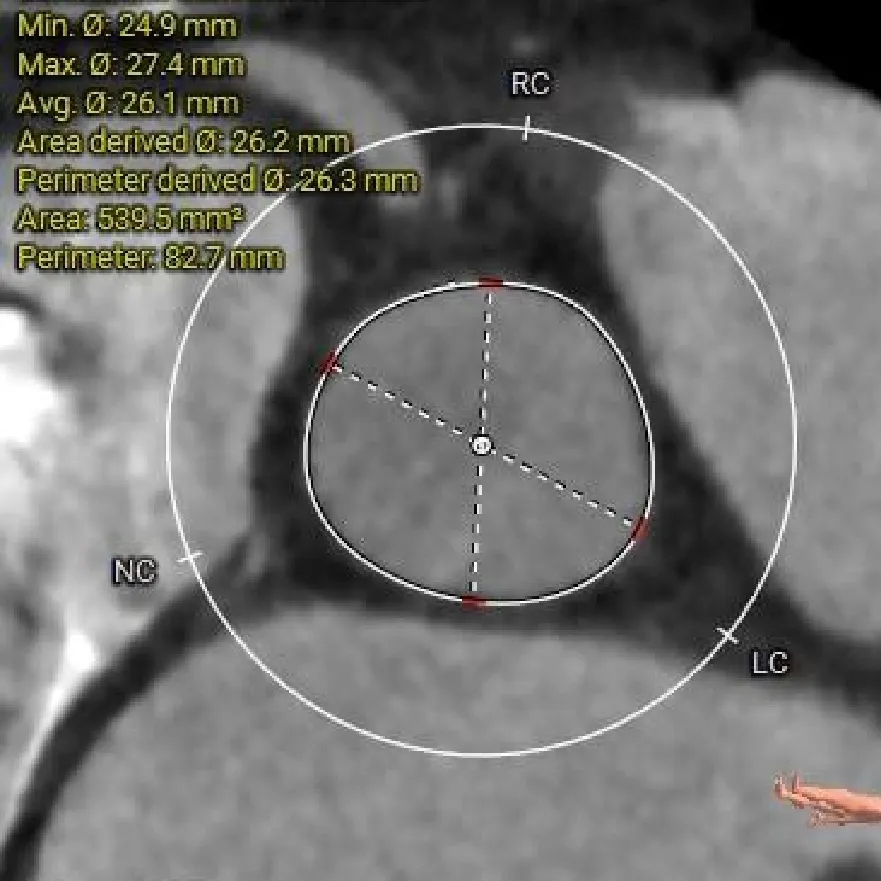

主动脉根部测量

Annulus

20.1mm

LVOT

19.9mm

三叶瓣,RL/RN高位纤维融合,瓣环偏大

-

瓣环直径约20.1mm,直筒型流出道

瓣叶增厚,中度钙化